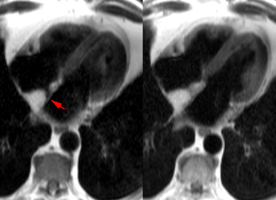

– Insuffisance mitrale : intérêt limité de l’IRM, quoique des approches quantitatives soient possibles.

– Les abcès annulaires infectieux ou froids calcifiés constituent de bonnes indications pour l’IRM cardiaque.

– L’IRM est un complément intéressant dans les suspicions de fibroélastomes (mais moins performant que l’ETO).